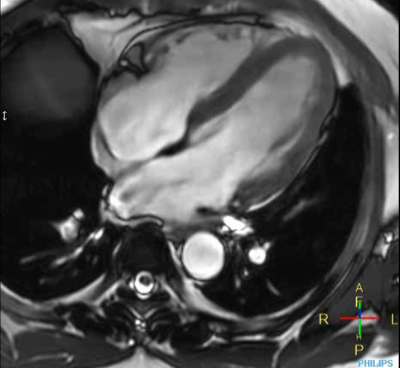

Cine 2D BFFE (4 CAV)

Elition X 3.0T